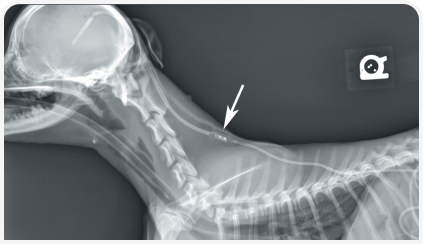

Радикальная терапия заключается в проведении хирургической операции по вентрикулоперитонеальному шунтированию.